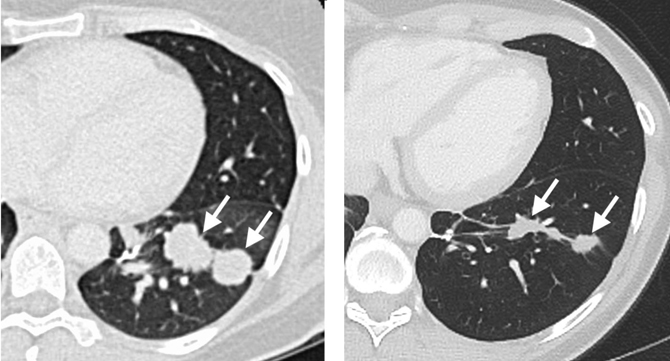

En la imagen puede verse el pulmón de la paciente antes y seis meses después de la ACT. / Jim Yang

En esta investigación, Rosenberg y su equipo analizaron los TILs de una enferma de cáncer de las vías biliares con metástasis en el pulmón y en el hígado que no había respondido a la quimioterapia estándar. La paciente, de 43 años de edad, fue inscrita en un ensayo de ACT en el Instituto Nacional de Salud de EE UU (NIH) para los pacientes con cáncer gastrointestinal.

Después, los científicos le dieron cuatro dosis del medicamento contra el cáncer interleucina-2 para mejorar la proliferación y la función de células T. Tras la transferencia de los TILs, los tumores metastásicos de hígado y pulmón de la paciente se estabilizaron. Transcurridos unos 13 meses, fue tratada de nuevo con ACT. En esta ocasión el 95% de las células transferidas eran células T mutantes.

Tras el tratamiento, la paciente experimentó una regresión del tumor seis meses después de la segunda infusión de células T. Los autores indican que estos resultados evidencian que se puede aprovechar la respuesta de las células T contra una proteína mutante para mediar el retroceso de un cáncer metastásico de células epiteliales.